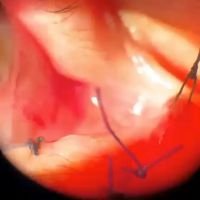

Catarata traumática por herida penetrante esclerocorneal

Dr. Agustin MiquelPuntos corneales para cierre primario, sinequiolisis con espátula, membranectomía, retractores de iris. -